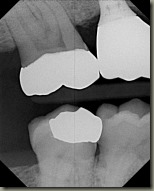

Dental Xrays

Photo credit: Martina at Rincon Dental

Teef 02

Composite